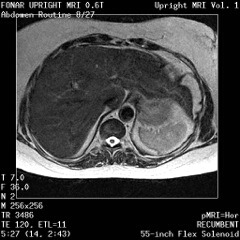

![]() |

The Liver, Kidney

and Small Intestine

|

Lumbar Spine |

Recumbent, Weightless |

Upright, Weight-Bearing |

Figure 8a-8d.

Further examples of the exceptional anatomic detail

made visible by the DISCOVERY

of Damadian of the pronounced differences in the decay

rates (relaxations) of the NMR signals

of the body's normal tissues (Figure

6). The DISCOVERED

differences supply the pixel amplitude differences

"PIXEL CONTRAST (IMAGE DETAIL)"

that produce, for the first time in medical history,

the detailed visualization of normal human anatomy

MRI is noted for. Note the visualization of the